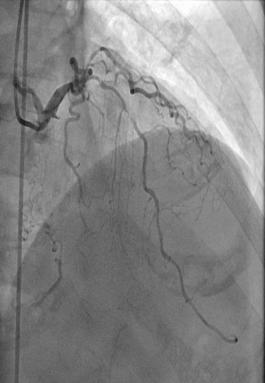

患者的左边血管堵塞也极其严重,主干道狭窄99%,合并钙化、弥漫、分叉,在预扩张球囊呈现明显的“腰征”的情况下,罗裕主任果断选择了旋磨治疗,1.5mm的磨头5次后通过,最后成功植入两枚支架。

左图术前左冠,右图术后左冠